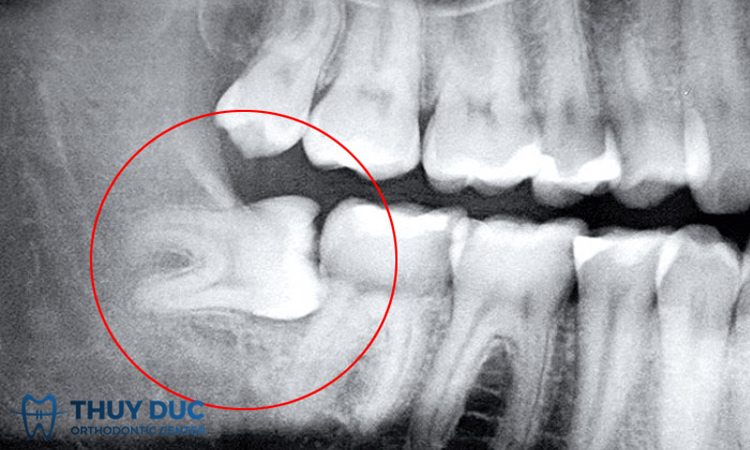

Răng khôn mọc lệch 90 độ là tình trạng răng không mọc lên theo phương vuông góc với xương hàm. Đây là một dạng răng khôn mọc lệch phức tạp khó xử lý cần xử lý sớm để tránh gây ra những hậu quả nghiêm trọng cho sức khỏe. Vậy răng khôn mọc lệch 90 độ ảnh hưởng xấu tới sức khỏe răng miệng tổng thể như thế nào? Cùng tìm hiểu trong phần dưới đây.

Ảnh hưởng tới răng số 7: Có thể nói trong các trường hợp răng khôn mọc lệch thì răng khôn mọc lệch 90 độ có nguy cơ ảnh hưởng nặng nề nhất tới răng số 7. Qua thời gian, răng số 8 phát triển lớn dần lên sẽ gây ra tình trạng va chạm với thân răng số 7, nguy cơ khiến răng số 7 bị sứt mẻ, lung lay và gãy rụng.

Tình trạng mọc răng khôn: Những điều cần quan tâm đầu tiên là mức độ phức tạp của chiếc răng khôn, kích thước, trạng thái của răng khôn sẽ thể hiện rõ trên hình ảnh chụp X-Quang. Chiếc răng khôn có kích thước càng lớn, nằm gần các dây thần kinh cảm giác thì mức độ nguy hiểm của ca nhổ răng khôn càng lớn hơn.